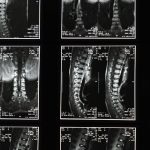

Traitements par imagerie: Utilisation de l’IRM pour un diagnostic précis et un suivi adapté.

Le bombement discal survient lorsque le centre d’un disque intervertébral se déplace légèrement hors de sa position initiale, tout en conservant son enveloppe externe intacte. Cela peut entraîner une pression accrue sur les nerfs environnants, se traduisant par des douleurs et des limitations de mouvement. Identifiez les symptômes associés, tels que des douleurs lombaires ou des engourdissements dans les membres, pour orienter vers les traitements appropriés.

Le bombement discal se produit lorsque le matériau gélatineux à l’intérieur d’un disque intervertébral se déplace légèrement, sans rompre l’enveloppe externe. Cette affection peut provoquer des douleurs, des raideurs et, dans certains cas, des symptômes neurologiques. Il est essentiel de comprendre les facteurs de risque et les causes sous-jacentes afin d’adapter au mieux le traitement.